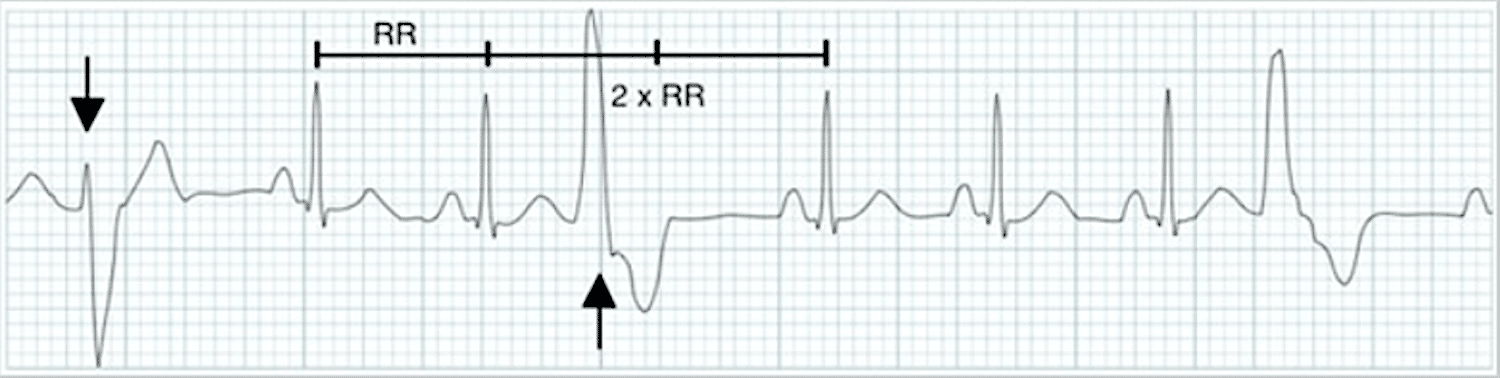

In the figure below, the arrows indicate PVCs. A dropped R wave follows the PVC. That compensatory pause does not affect the core rhythm because the SA node discharges at its own pace.

ECG tracing displays PVCs with a dropped R wave.